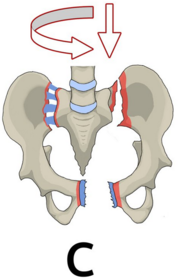

Typ C Instabile Beckenringsfraktur mit Rotations- & Translationsinstabilität. Komplette Instabilität des hinteren Beckenrings, Rotationsinstabilität einer Beckenseite.

Was bedeutet komplette Instabilität? Durch Fraktur des vorderen und hinteren Beckenrings kommt es zur völligen Instabilität des Beckens (sowohl horizontale als auch vertikale Krafteinwirkung führt zum Auseinanderweichen des Beckens).

Was sind Beispiele für Typ C? Nenne drei: a) Schädigung von Os sacrum, -ilium oder Iliosakralgelenk sowie Symphysensprengung/vordere Beckenringfraktur b) C-Fraktur + B-Fraktur auf der Gegenseite c) Beidseitige C-Fraktur

Wie sehen Frakturen Typ A - C aus?